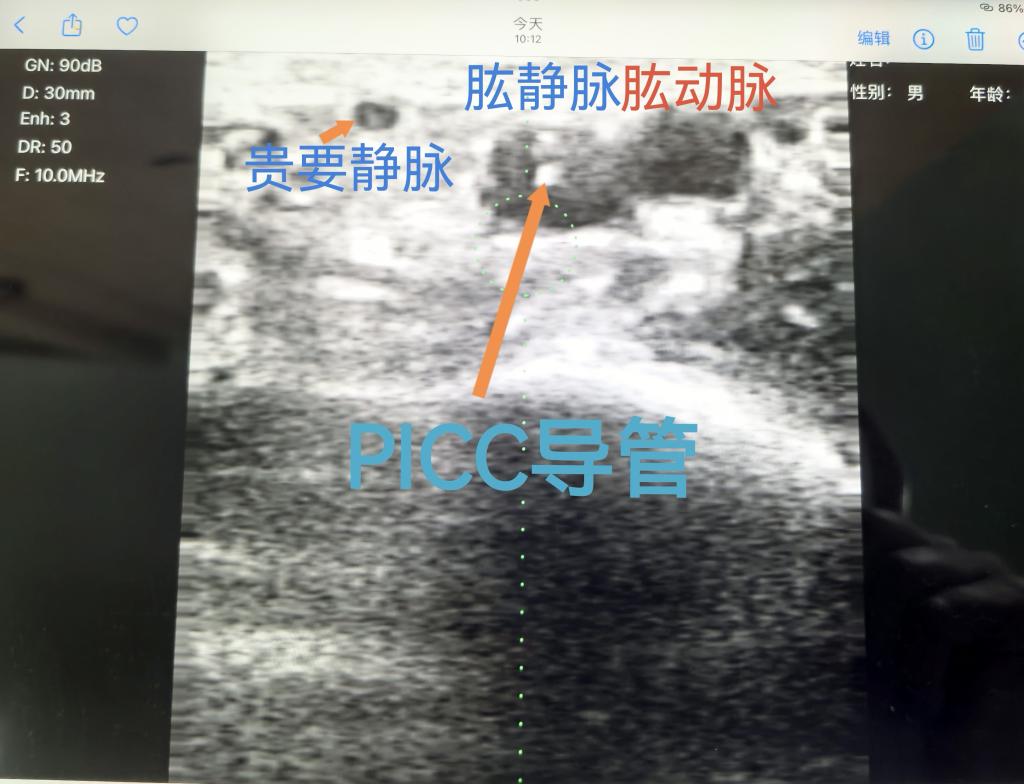

经过对老人身体和血管条件的充分评估后发现,老人首选的贵要静脉极细,肩关节和肘关节活动度减弱,不能配合手臂外展姿势,大大增加操作的难度。B超下看到老人极细的贵要静脉,果断选择肱静脉,但肱静脉与动脉并行,穿刺过程中误伤动脉的风险很大,这就要求操作者具备更高的技术水平和丰富的穿刺经验。顶着巨大压力,杨敏娟护士迎难而上,在刘倩副护士长的协助下,一个人固定患者的手臂姿势,关注者老人的状态,一个人沉着冷静地穿刺,一针见血,在左上肢肱静脉成功留置PICC导管,老人的儿子激动的为我们的护理技术竖起了大拇指。